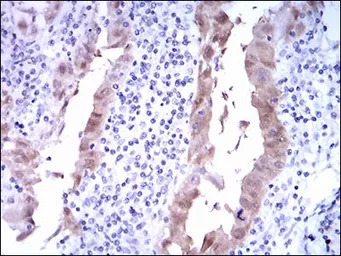

IHC-P analysis of lung cancer tissue using GTX60663 CDKN2A / p16INK4a antibody [1D7D2].

IHC-P analysis of endometrial cancer tissue using GTX60663 CDKN2A / p16INK4a antibody [1D7D2].